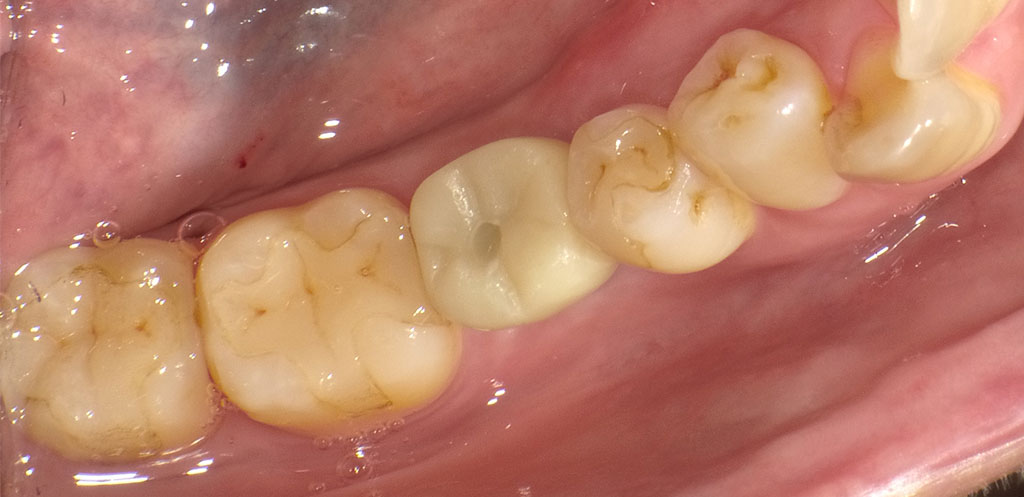

Before1

Before2